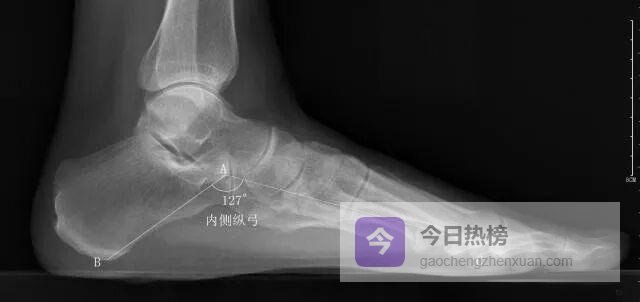

4.2 ◆ 四大角度测量法 4.2.1 ◆ 内侧纵弓角以距骨头最低点为原点,向跟骨最低点与第1跖骨头最低点各引一条水平线, 测量两线夹角。

内侧纵弓角<113°或>130°;